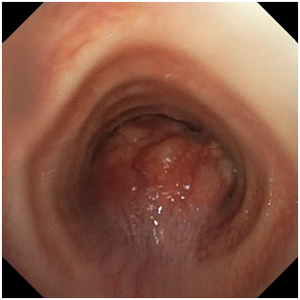

全麻下气管镜检查提示:气管管腔中段可见菜花状新生物形成,几近完全阻塞气管。病灶基底部宽大,不适宜应用硬质气管镜铲切,遂应用电圈套器圈套、氩气刀、针状电刀、冷冻(冻切及冻溶)、球囊扩张等治疗。

治疗前后对比